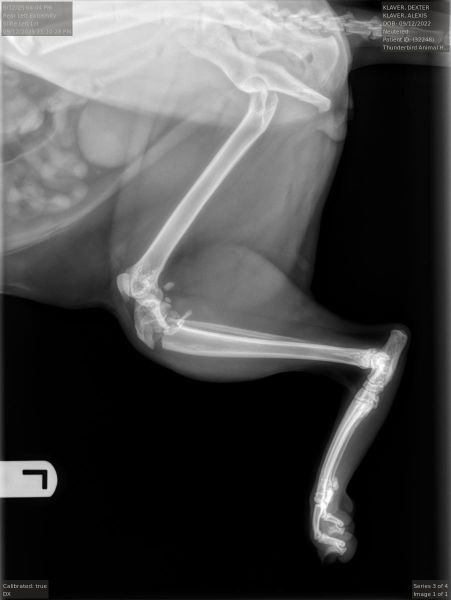

I was hoping to get an opinion whether my cats fractures will heal. He is thought to have been hit by a car and has tibial fractures of both hind legs below the proximal joint. We could not afford the 6000$ surgery to fix them and are splinting instead. I am wondering what the chances are that they will heal? He is eating and drinking, and appears comfortable. Stifle_Left_LatStifle_Right_Lat Thank you

Hello and I'm sorry to read about your kittens problems.   Those radiographs look so uncomfortable!    They are in a very delicate part of the joint and we would recommend that yourself or your vet has an initial chat to an orthopaedic surgeon, specialists in such cases.   Good questions include 'What will be involved in recovery?' And 'What quality of life can I reasonably expect in each case?'